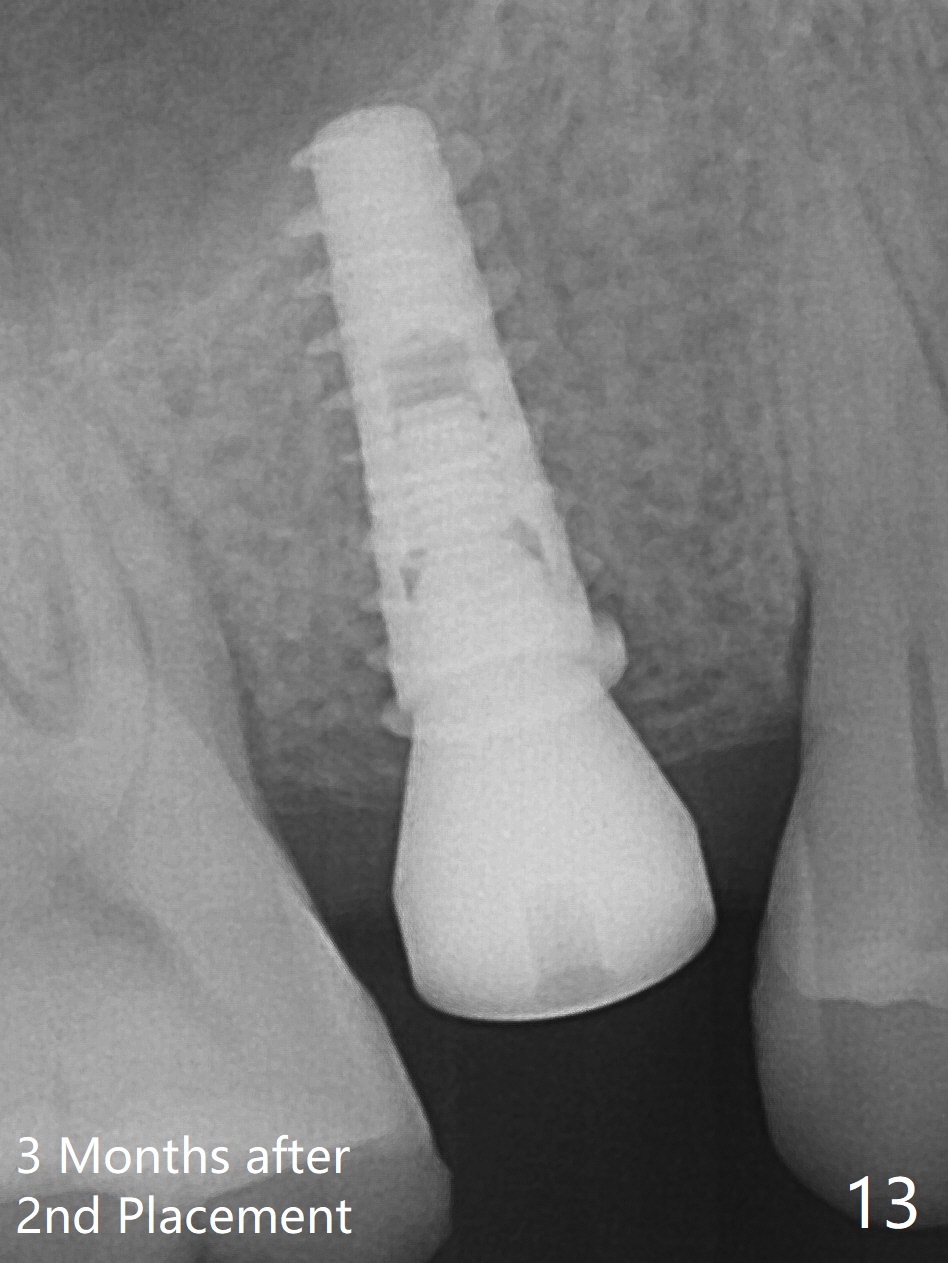

A 47-year-old man returns emergently with subgingival fracture of the lingual (L) cusp of the tooth #4 (Fig.1-3). After extraction (no bony defect) without drilling, a 4x11 mm dummy implant is placed as a tap drill with satisfactory stability (Fig.4,5). To get subcrestal placement, a shorter (4x9 mm) implant is inserted with insertion torque of < 35 Ncm. In retrospect, a larger implant (4.5 mm) would be better in term of primary stability. After allograft placement into the buccal and lingual gaps, a 4.5x4(4) mm abutment is placed for an immediate provisional. There is a peri-implant gap 7 months postop (Fig.7<, as compared to the implant at #2 (6 months postop)) . When the loose abutment is being retightened, the patient feels pain, although the gingiva appears healthy (Fig.8). A larger implant should have been used; the abutment should have been removed. The implant dislodges while the abutment is untightened 8 months postop. The osteotomy is found intact. A 4.5x11 mm dummy implant is placed 2 mm subgingival with 20 Ncm (Fig.9). When a 4.5x11 mm definitive implant is placed 3 mm subgingival (Fig.10,11), torque reaches 50 Ncm. A 5.5x3 mm healing abutment is placed. Three months postop, the implant is stable (Fig.12,13) and impression is taken.